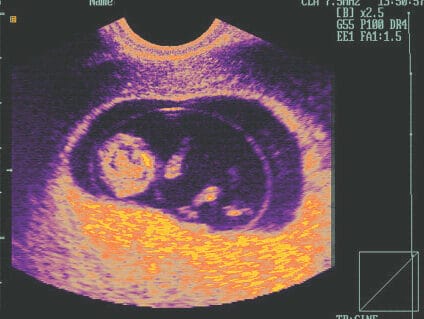

El ultrasonido obstétrico es una técnica utilizada durante el embarazo que permite observar y evaluar el desarrollo del feto en el útero materno. Esta herramienta médica utiliza ondas sonoras de alta frecuencia para crear imágenes en tiempo real del bebé, la placenta y el útero de la madre.

El ultrasonido obstétrico se ha convertido en una práctica común dentro del contexto de la atención prenatal. No solo proporciona información sobre la edad gestacional y el crecimiento fetal, sino que también permite detectar anomalías y malformaciones congénitas. Además, brinda la oportunidad de conocer el sexo del bebé, lo cual es un momento emocionante para los futuros padres.

El ultrasonido 4D es una técnica más avanzada que permite obtener imágenes tridimensionales en tiempo real, lo que brinda una representación más detallada y realista del feto. Esto ha permitido a los padres tener una experiencia más cercana y emocional al ver el rostro y los movimientos de su bebé antes de su nacimiento.